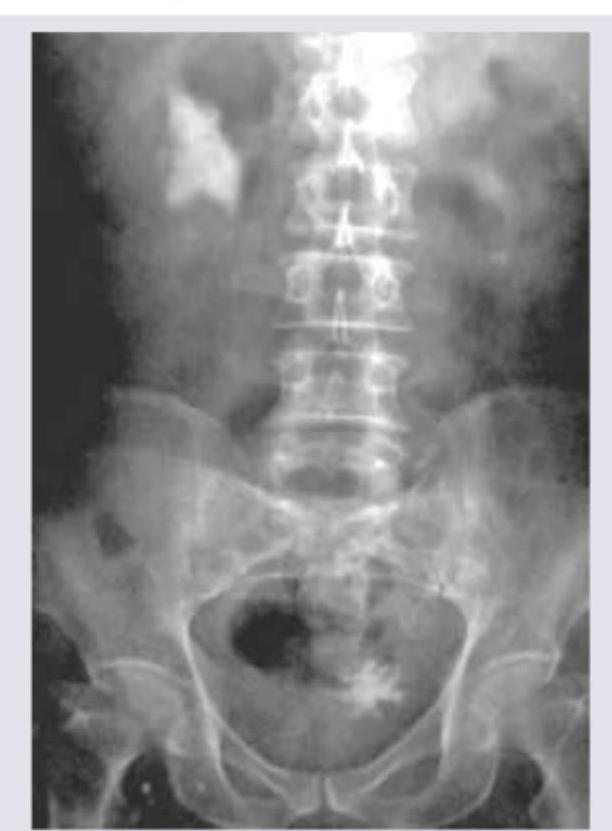

Question 3: Which is incorrect about the procedure shown in the patient with right flank pain?

Explanation: In the provided image, there is a large, irregularly shaped, radio-opaque density in the right renal area, consistent with a **staghorn calculus**, likely causing the right flank pain. This type of calculus typically fills the renal pelvis and calyces. The question asks what is *incorrect* about the procedure shown, referring to **Extracorporeal Shockwave Lithotripsy (ESWL)**, a common treatment for kidney stones. ***Correct: No anesthesia is required*** - This statement is **incorrect** and is the correct answer to this negation question - ESWL typically requires some form of **analgesia or sedation** (e.g., intravenous fentanyl, midazolam, or even general anesthesia in selected cases) - The shockwaves cause significant discomfort as they are delivered, making **pain management essential** for patient comfort and compliance - While some patients with high pain tolerance may undergo the procedure with minimal analgesia, most require sedation *Incorrect: Contraindicated in hard stones* - This statement is partially correct, making it NOT the best answer - While hard stones (e.g., **calcium oxalate monohydrate, cystine, brushite**) are **more resistant** to ESWL with lower stone-free rates, ESWL is **not absolutely contraindicated** - ESWL can still be attempted for hard stones, though it may require multiple sessions, higher energy settings, or may ultimately fail, necessitating alternative treatments like **ureteroscopy** or **percutaneous nephrolithotomy (PCNL)** - True contraindications include pregnancy, uncorrected bleeding disorders, obstruction distal to the stone, and severe skeletal deformities *Incorrect: Done as outpatient procedure* - This statement is **correct** about ESWL, so it is NOT the answer to this negation question - ESWL is routinely performed on an **outpatient basis**, with patients typically going home the same day - Patients are monitored for a short period post-procedure (usually 1-2 hours) to ensure there are no immediate complications like significant hematuria or pain before discharge - Rarely, patients may require overnight observation if complications arise *Incorrect: Shockwaves pass through a water bath* - This statement is **outdated** but historically accurate - **First-generation ESWL machines** (1980s) utilized a **water bath** in which the patient was partially submerged to couple the shockwaves - **Modern lithotripters** (second and third generation) use a **gel pad** or **water cushion** placed directly on the skin, eliminating the need for water immersion while maintaining acoustic coupling - While technically incorrect for modern ESWL, the statement was historically true, making "no anesthesia required" a more definitively incorrect statement